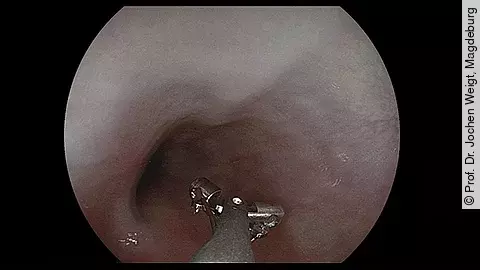

Endoskopisches LehrvideoGezielte Biopsieentnahme im Ösophagus

Wie entnimmt man im Ösophagus am besten gezielte Biopsien und welche Schritte sind dabei entscheidend? Genau das zeigt Ihnen PD Dr. Jochen Weigt vom Universitätsklinikum Magdeburg im neuen Video.